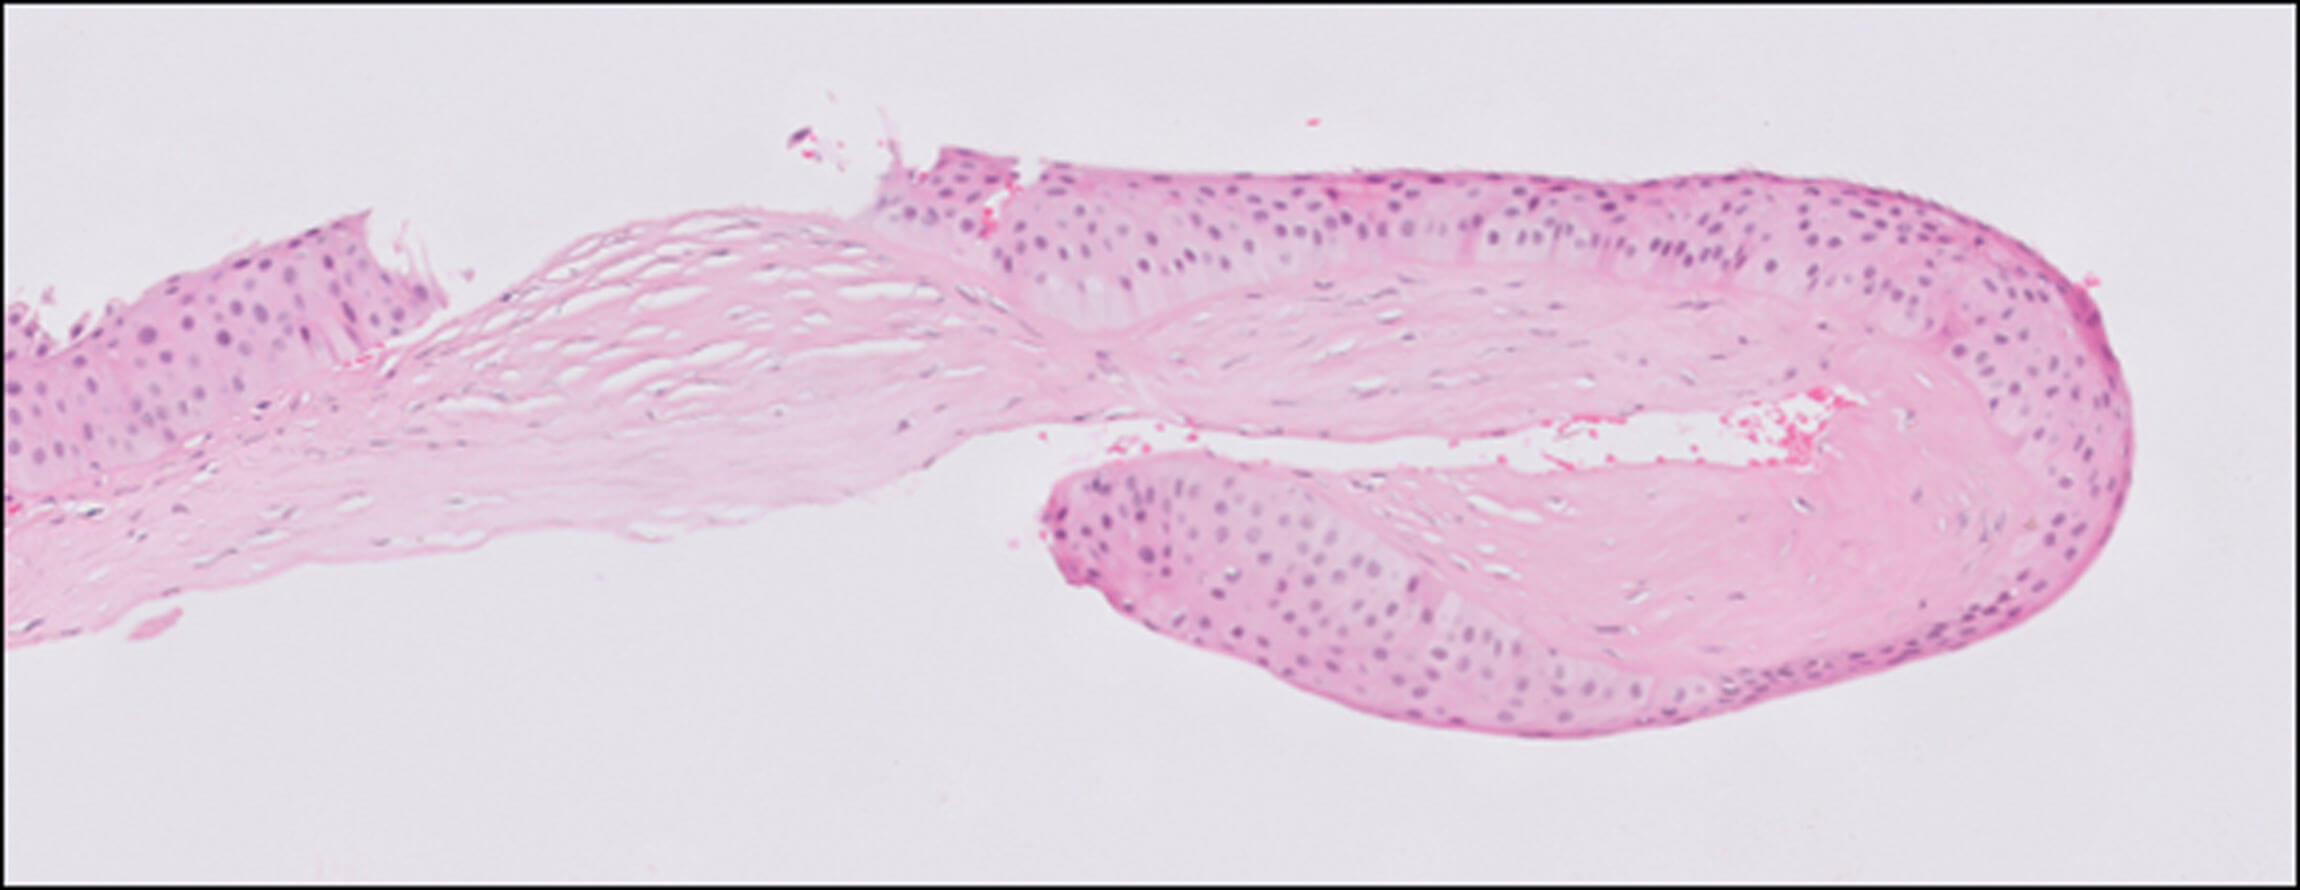

- Figures 1-3 show representative H+E and diastase-periodic acid Schiff (DPAS) stained sections of the lesion. How can this be described?

- The specimen comprises corneal epithelium with superficial anterior stroma. The epithelium is markedly attenuated over nodular areas of hyalinised, condensed collagen. Bowman’s layer is absent (Figures 1 and 2). DPAS staining highlights the slightly thickened subepithelial basement membrane, the nodular areas, and the irregularity of collagen fibres elsewhere.